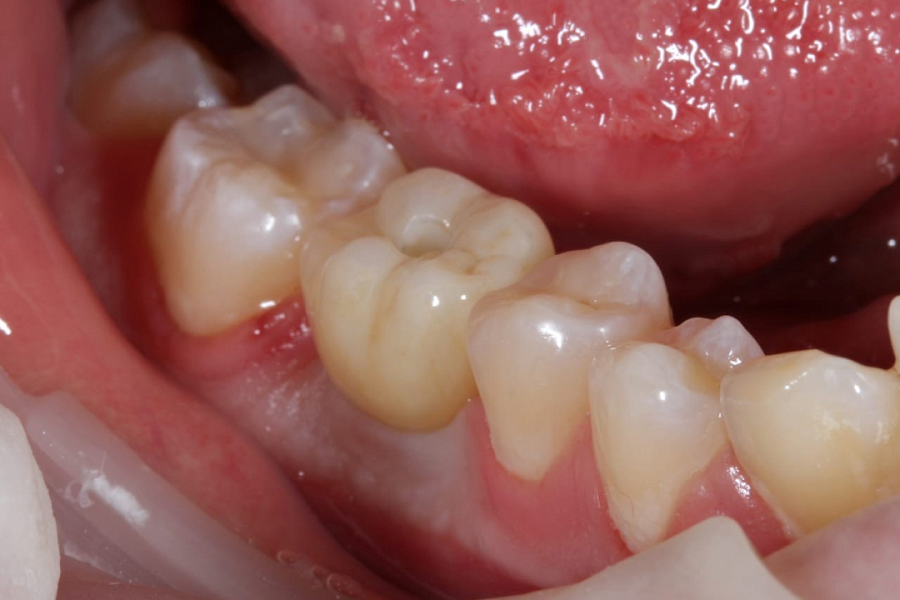

Пациент направлен врачом-терапевтом для удаления зуба 46 (нижний шестой зуб справа) и одновременной постановки имплантата.

Зуб был фрагментирован, чтобы удаление прошло максимально атравматично, то есть без повреждения окружающих костных стенок. После удаления установлен имплантат. Операция прошла успешно, пациенту уже установлена зубная коронка.